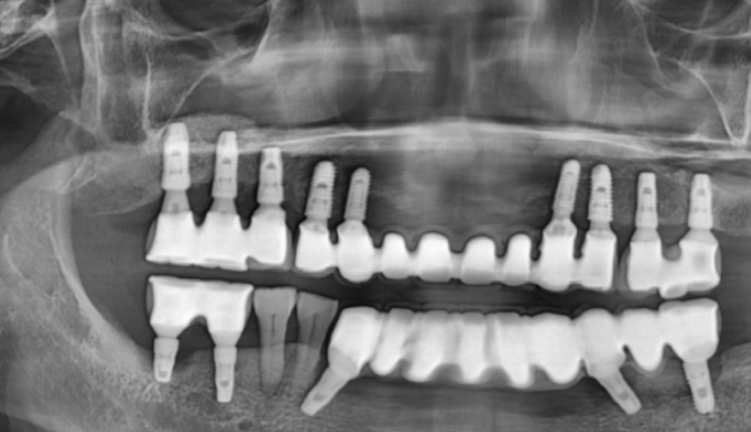

치과를 찾아와주신 오늘의 환자분

엑스레이 사진에서도 보이지만

치료를 참 많이 하신 환자분입니다.

전악 임플란트를 하셨고

남아있는 내 치아는 딱 2개

오른쪽 아래 작은 어금니만 본인 치아셨습니다.